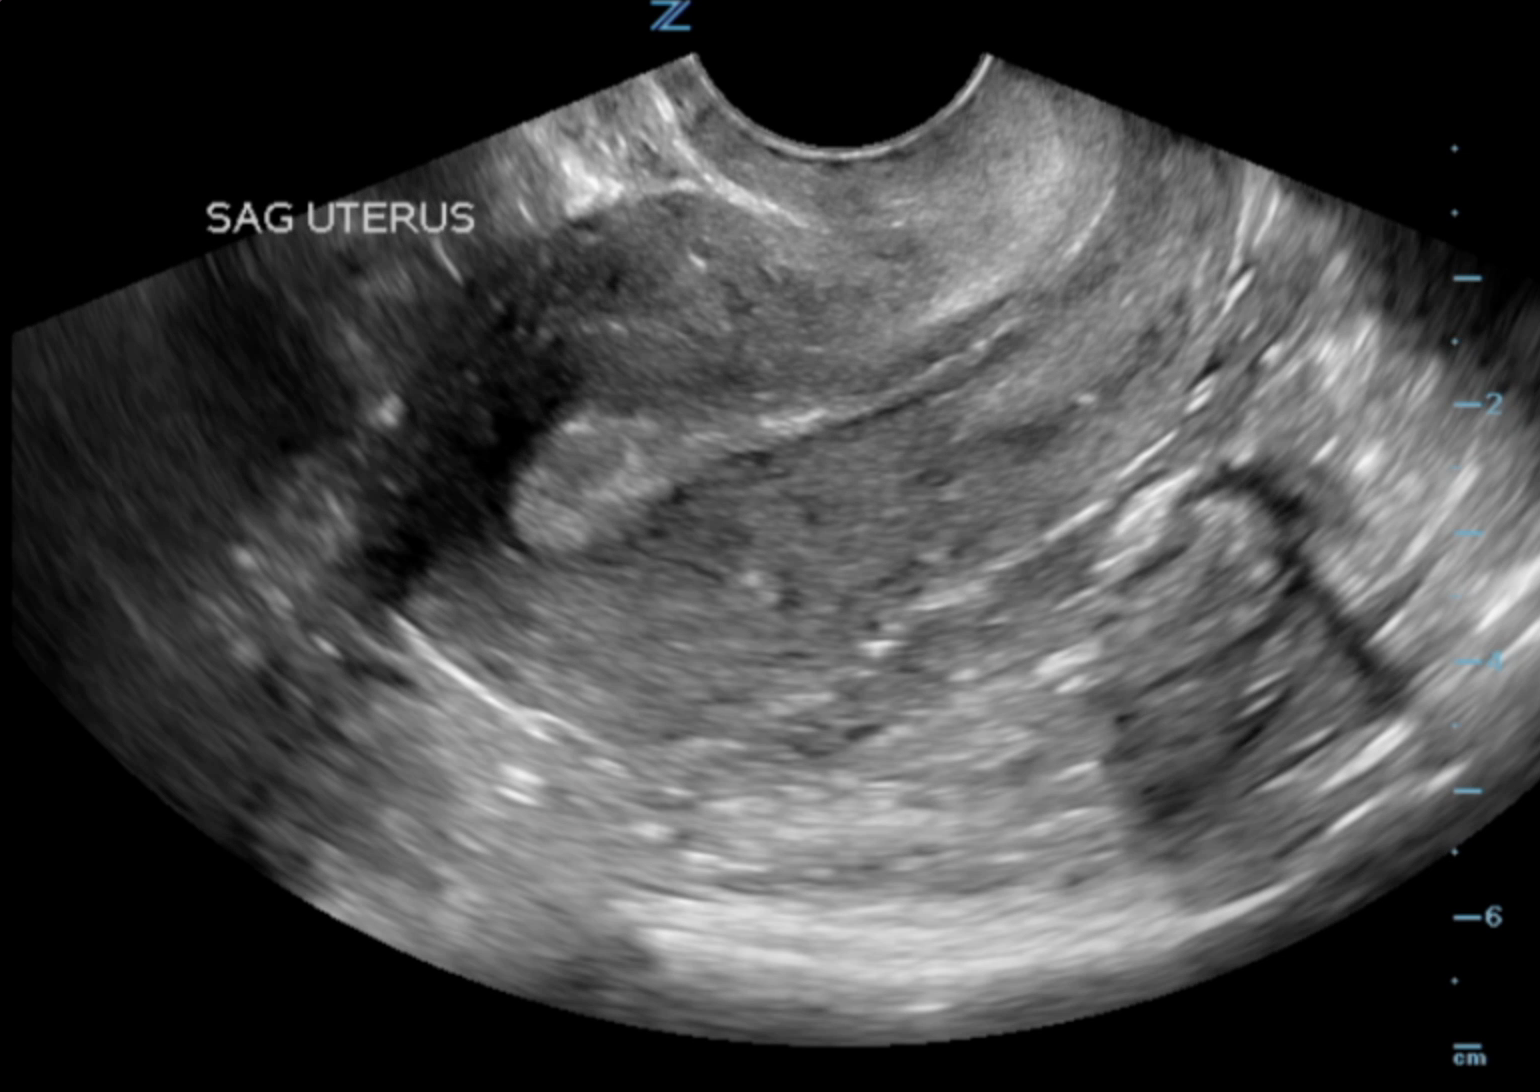

- Insert or have the patient insert the probe into the vagina with probe indicator towards to ceiling. This is the sagittal/longitudinal plane. (Illustrations 7 and 8)

- Fan right to left to view the entire uterus.

- Illustration 8. Image of transvaginal sagittal/longitudinal view. Notice hyperechoic (bright) endometrial stripe.